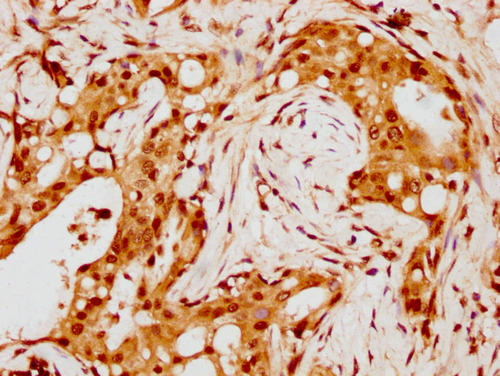

• IHC image of CSB-PA010429PA88nohHU diluted at 1:8 and staining in paraffin-embedded human breast cancer performed on a Leica BondTM system. After dewaxing and hydration, antigen retrieval was mediated by high pressure in a citrate buffer (pH 6.0). Section was blocked with 10% normal goat serum 30min at RT. Then primary antibody (1% BSA) was incubated at 4°C overnight. The primary is detected by a biotinylated secondary antibody and visualized using an HRP conjugated SP system.